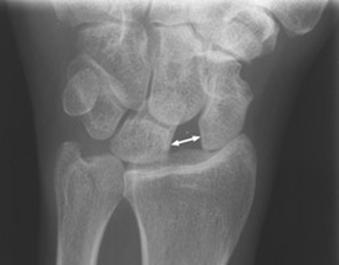

Largirea articulatiei scafo-lunare Fractura

Galeazzi

Semnul Terry Thomas